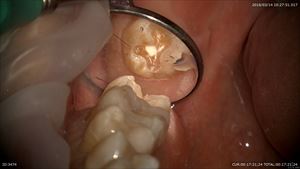

感染を取り

この部分だけ深いので手作業